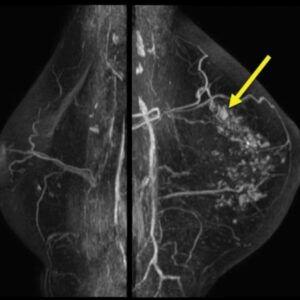

Breast cancer seen in an mri

Breast cancer seen in an MRI with yellow arrow pointing to an 0.8-cm ductal carcinoma. Credit: Radiological Society of North America